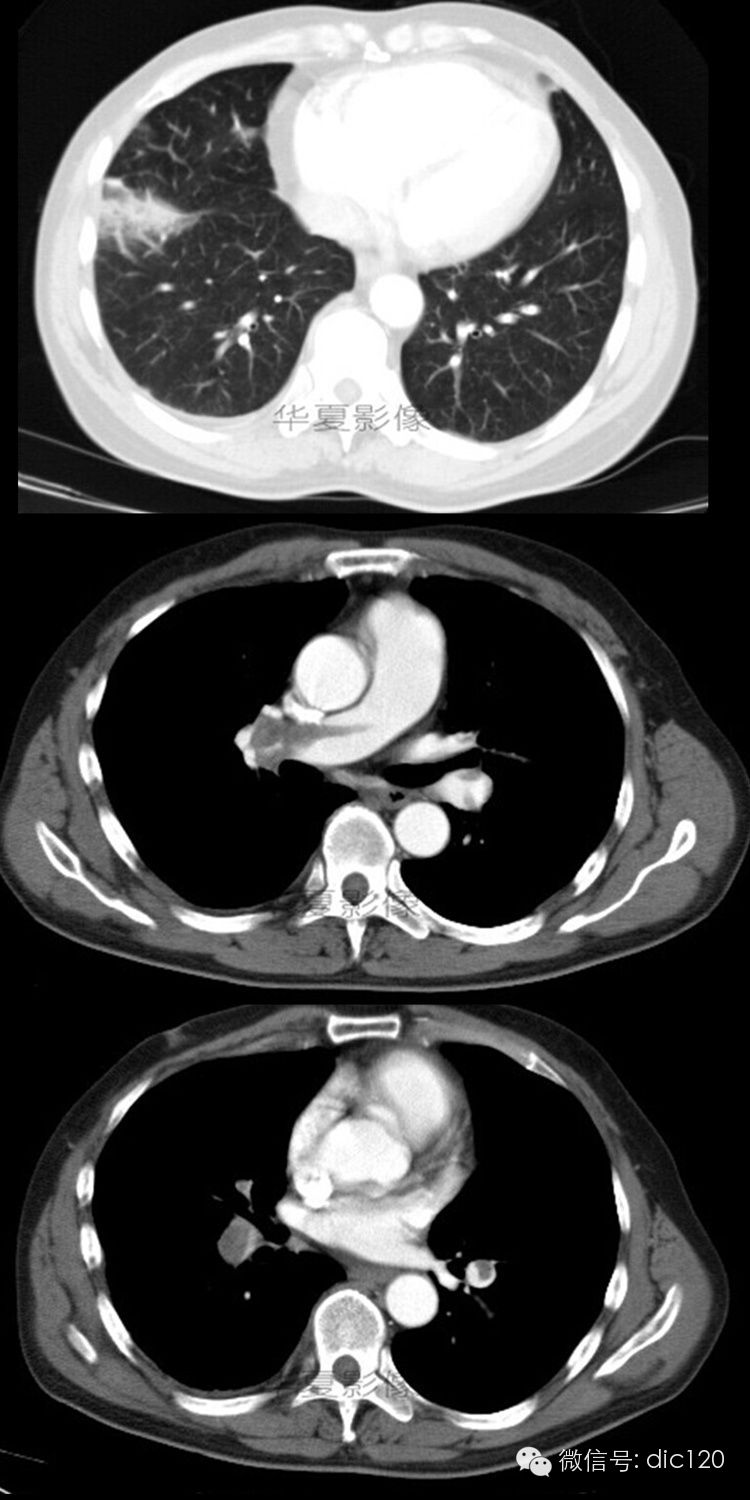

男,56岁;咳嗽、咳痰胸痛4天。

右肺下叶前基底段见胸膜下楔形高密度影,尖端指向肺门,部分边界清楚;增强后肺动脉及其各大分支内可见条带状无强化充盈缺损征。

诊断依据:典型影像表现,对症治疗后病灶明显缩小,部分消失;临床症状好转。

肺动脉内有栓子是诊断肺动脉栓塞最可靠的征象,增强后栓子不强化,栓子的形态和栓塞的程度不同,CT表现也各异。血栓位于血管腔中心呈长条状与血管腔平 行,当栓子与扫描层面平行,中央的栓子则呈条状低密度带,两边有含有对比剂的血流,二者形成鲜明的对比,即呈“轨道征”;栓塞的血管远端呈低密度而无对比 剂充盈,出现典型的“血管截断征”;血管腔一侧出现偏心性充盈缺损,对侧充盈高密度对比剂;当梗死灶形成后,表现为胸膜下楔形或片状软组织密度,尖端指向 肺门;有时还可以见到肺动脉高压和胸腔积液等征象。